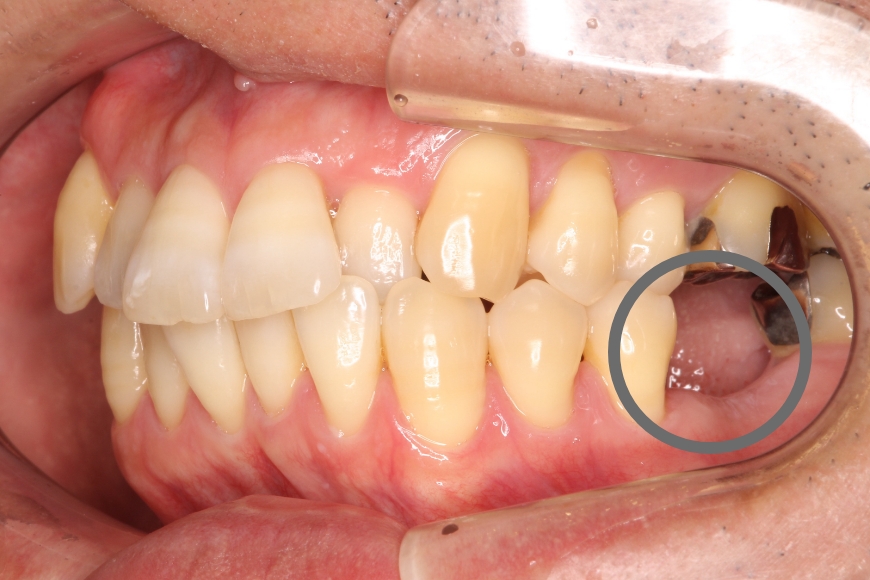

50代女性 左右の奥歯へのインプラント治療

治療内容 下の左右の奥歯が無く、食事がうまくできないことを主訴に来院されました。

左右の奥歯に2本ずつインプラント治療を行いました。奥歯でしっかりと噛めるようになりました。

治療期間・回数 治療期間:約6ヶ月

通院回数:10回程度

治療費用(総額)

1,760,000

(1本440,000円×4本分。時期や手法により異なる場合があります。)